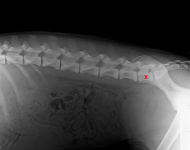

MVDr. Meloun: Lumbosakrální přechodový obratel